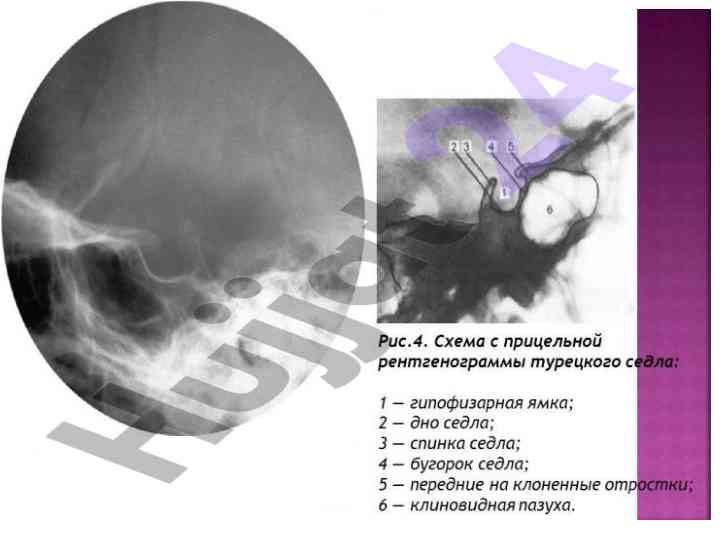

Gipofiz bezining kasalliklari, anatomiyasi va diagnostikasi haqida ma'lumotlar. Endokrin sistema va gormonlar haqida tahlil.